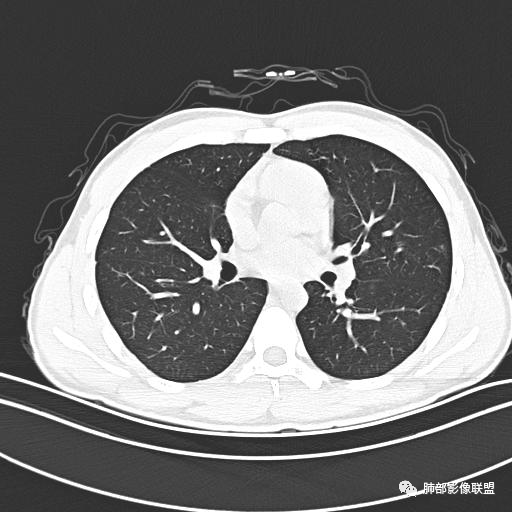

小强:青年,发热,皮疹;双肺散在结节,周围磨玻璃,点晕征,疱疹病毒感染,鉴别荚膜组织胞浆菌,结核。 大雄:青年,急性起病,发热伴全身皮疹2天,抗病毒治疗体温有下降。双肺随机分布大小不等类圆结节,“点晕征”。考虑水痘-疱疹病毒(VZV)血播询问接触史,查体皮疹分布以及形态基本可诊断。 王开金江津中心医院呼吸科:青年男性,起病急,病程短,以发热,皮疹为首发症状,感染指标以单核细胞升高为主,胸部ct双肺多发结界,周围有晕,点晕表现,随机分布,同意於老师意见,水痘疱疹病毒血流感染累及肺。 王秀仙:双肺多发大小不等结节,周围有晕,边缘模糊,呈点晕征表现。青年,急性起病,发热伴全身皮疹2天,抗病毒治疗体温有下降。考虑疱疹病毒。鉴别荚膜组织胞浆菌。 傅昌瑜:19岁男性,发热、全身皮疹2天,单核细胞增高,双肺多发结节,结节边缘见边界不清磨玻璃影。点晕征+发热、全身皮疹+单核细胞增高——考虑水痘-带状疱疹病毒肺炎。 一切∮随缘:年轻男性,发热,皮疹两天,实验室,CRP,PCT增高,影像:双肺多发散在磨玻璃结节,边界欠清,大小不等,呈点晕征改变,以血管束周围分布为主,局部血管束略增粗,其它无明显改变,考虑:1:病毒性肺炎(水痘疱疹病毒?不知道皮肤有无改变)2:真菌(组织胞浆菌,血管侵袭性肺曲霉)3:GPA4:寄生虫(实验室没有看到嗜酸细胞增高) 赵山河:双肺散在结节,周围有晕,边缘模糊,呈点晕征表现。青年,急性起病,发热伴全身皮疹2天,抗病毒治疗体温有下降。考虑水痘—疱疹病毒感染。洪桥爱:青年男性,发热、皮疹2天,伴瘙痒,皮疹于面部首发,之后进展至全身,虽然没有对皮疹进行描述,但是从出疹时间及皮疹进展情况,伴瘙痒,应该就是个水痘患者;CT提示双肺随机分布结节影,部分结节伴有边界不清晕征,考虑水痘血播肺。 刘强:年轻男性,急性起病,皮疹,发热,抗感染治疗体温下降,说明有效。影像表现为散在点晕征,感染类疾病谱(疱疹病毒,真菌,结核),结合年龄,皮肤皮疹,考虑水痘-疱疹病毒性肺炎。 小兜:男性,19岁,发热皮疹两天,颜面部至全身,CRP,降钙素及单核增高。CT示双肺散在小结节,周围伴磨玻璃影,点晕征,考虑为水痘-带状疱疹病毒(varicella-zoster virus,VZV)肺炎 必有路:青年,皮疹+发热+“点晕征”→水痘-疱疹病毒(VZV) 许慧良:青年男性患者,发热、皮疹2天,体温最高38.5℃,第3天皮疹扩展至全身,伴瘙痒,胸部CT:双肺多发随机分布的小结节,结节周边见边界模糊的晕征,考虑水痘病毒感染流心明智:男,19,急性起病,发热伴全身皮疹2天。出疹顺序头→全身,抗病毒有效。胸部CT:两肺多发大小不等类圆形实性小结节影,随机分布,结节周围环绕GGO,边界模糊,呈点晕征。出疹特点是关键,未提示。考虑:血播病毒性肺炎,水痘-疱疹病毒?麻疹?鉴别荚膜组织胞浆菌、TB、血管炎、寄生虫等。 浪迹天涯:病灶多为5-10mm大小结节,结节周围可见磨玻璃样的晕环,常多发,可分布于肺内任何区域,考虑水痘—带状疱疹病肺炎如果短时间内有新的一个区域浸润,更加能说明,